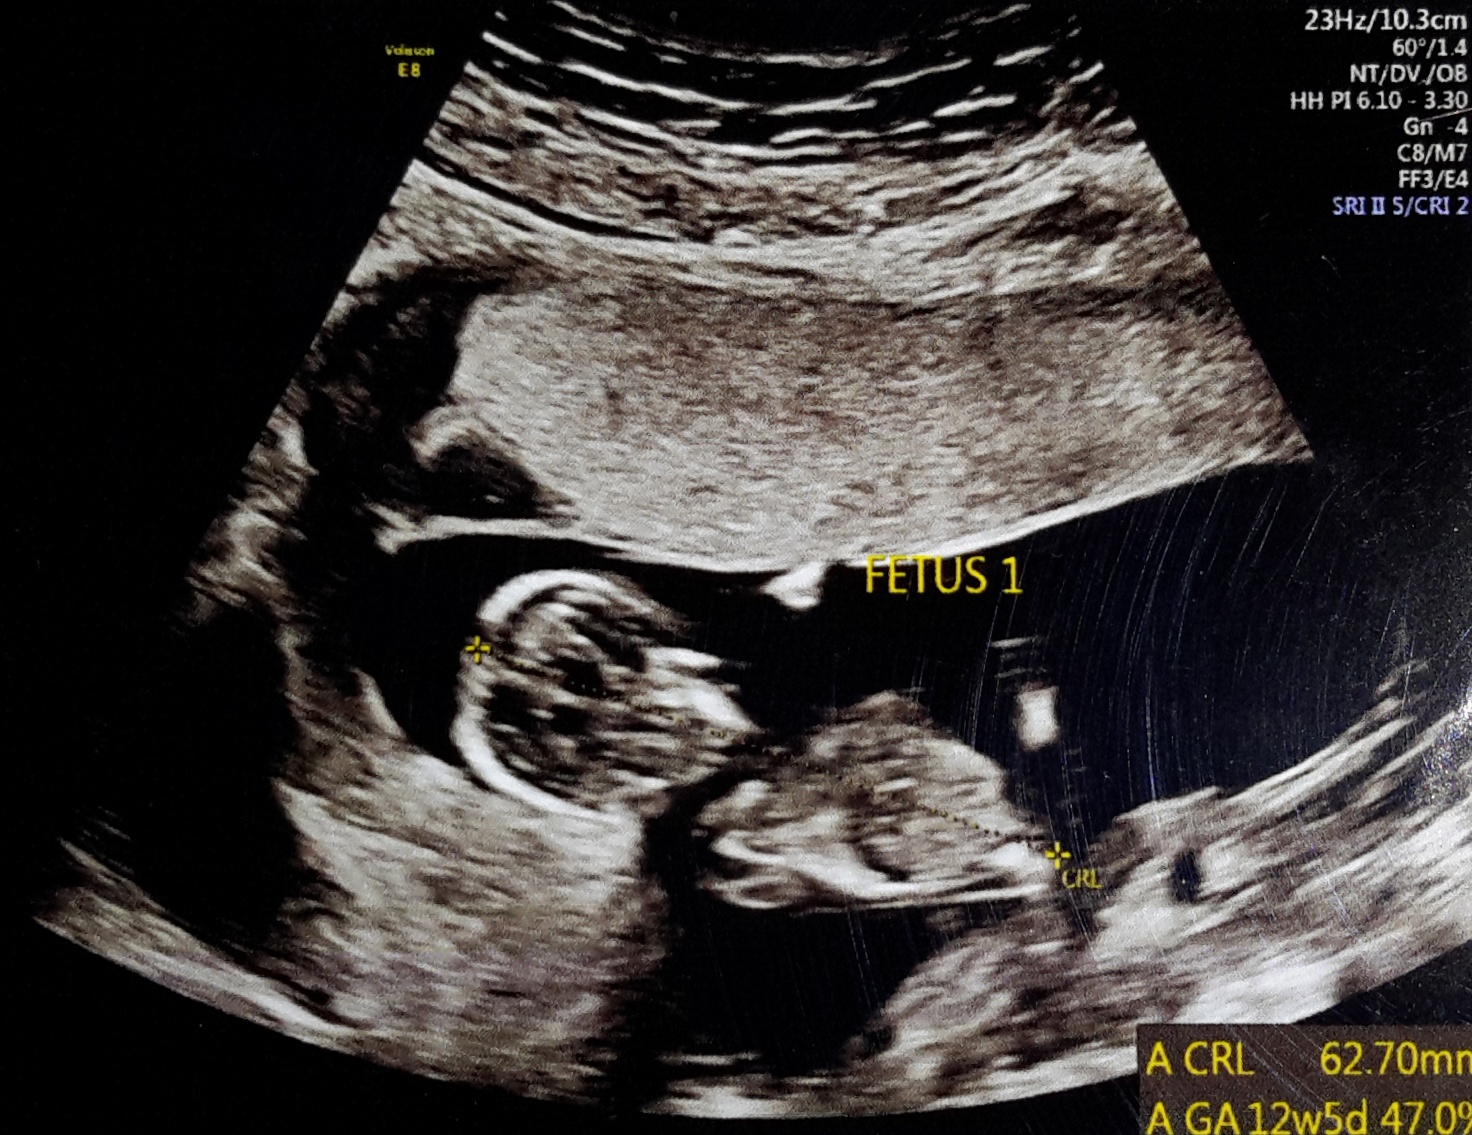

Here we go. 12 weeks ultrasounds

Attachment 40166

Attachment 40167

No nub on baby #1's pic but for baby #2 I see a bit of the nub. Maybe boy? It's so hard to tell as baby is curled up and the nub looks a bit cut off at the end.